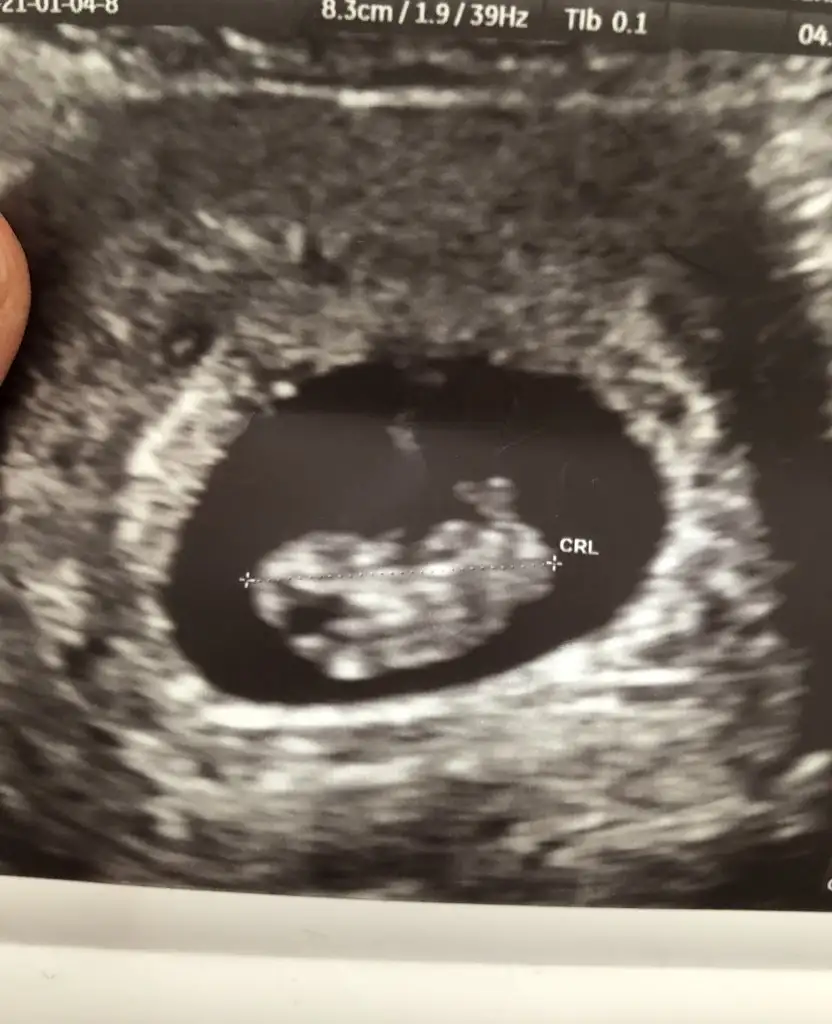

Daha çok küçük ama cinsiyetini çok merak ediyorum❤

Ilk bebişim cinsiyetin önemi yok tabiki ama ister istemez merak ediyorum banada tahminde bulunabilirmisiniz ❤ Çok erken ama keseden falan tahmin yapanlar oluyor diye paylaştım.